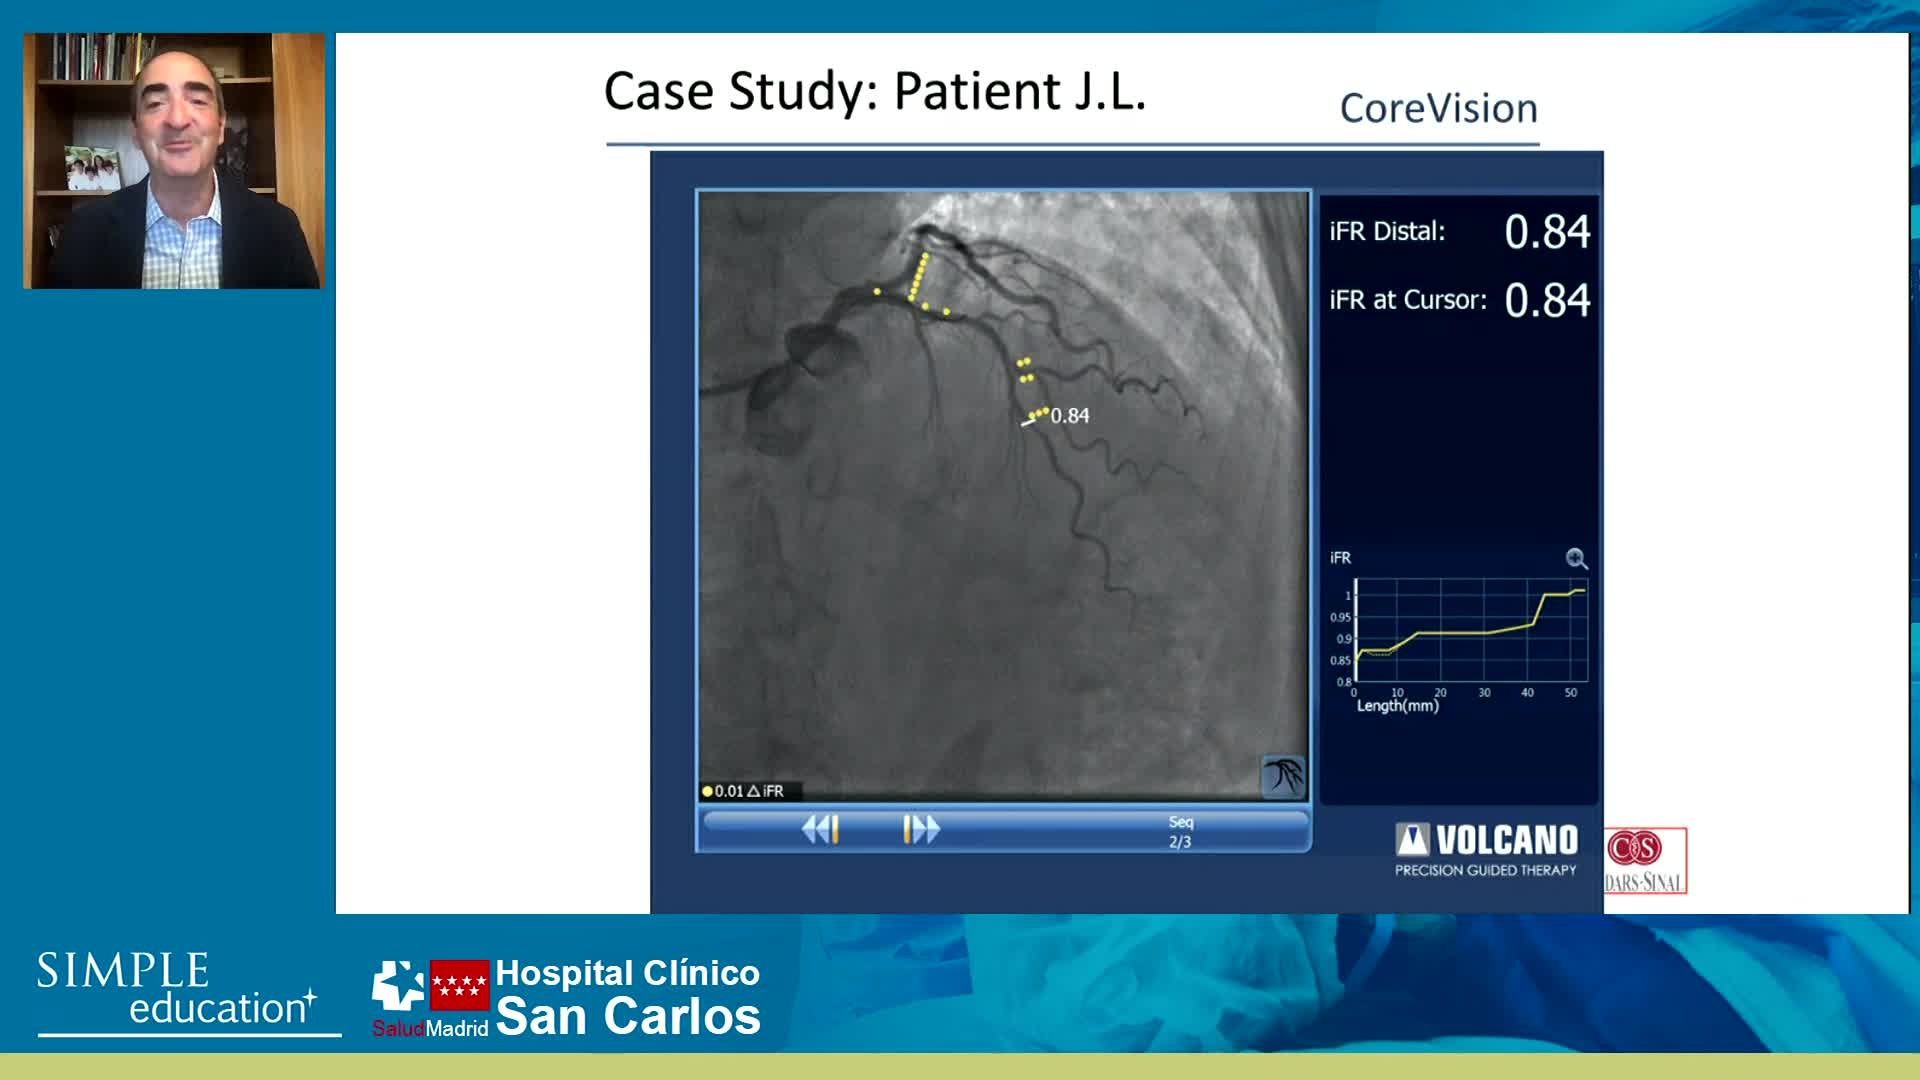

Using SyncVision Co-registration to distinguish between focal and diffuse coronary disease. - Prof Giuseppe Tarantini

Essential steps for physiology-based PCI planning and guidance - Dr Allen Jeremias

Best practices and personalised medicine in complex PCI - Prof Javier Escaned